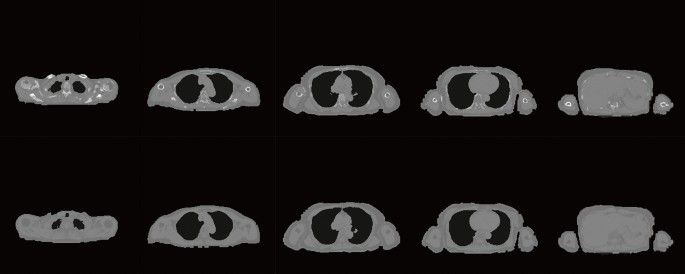

The upper row of Fig. 6 shows the synthesised CT based on the combination of the proposed method and conventional four-tissue segmentation, and the lower row shows the synthesised CT based on conventional four-tissue segmentation. The lower row images are clinically used for attenuation correction of PET/MRI. The upper row shows bone structures, which could not be synthesised using the conventional synthetic method (the lower row).

The upper row shows the combination of U-GAT-IT + MIND and conventional four-tissue segmentation. The lower row shows the synthesised CT based on the conventional four-tissue segmentation.